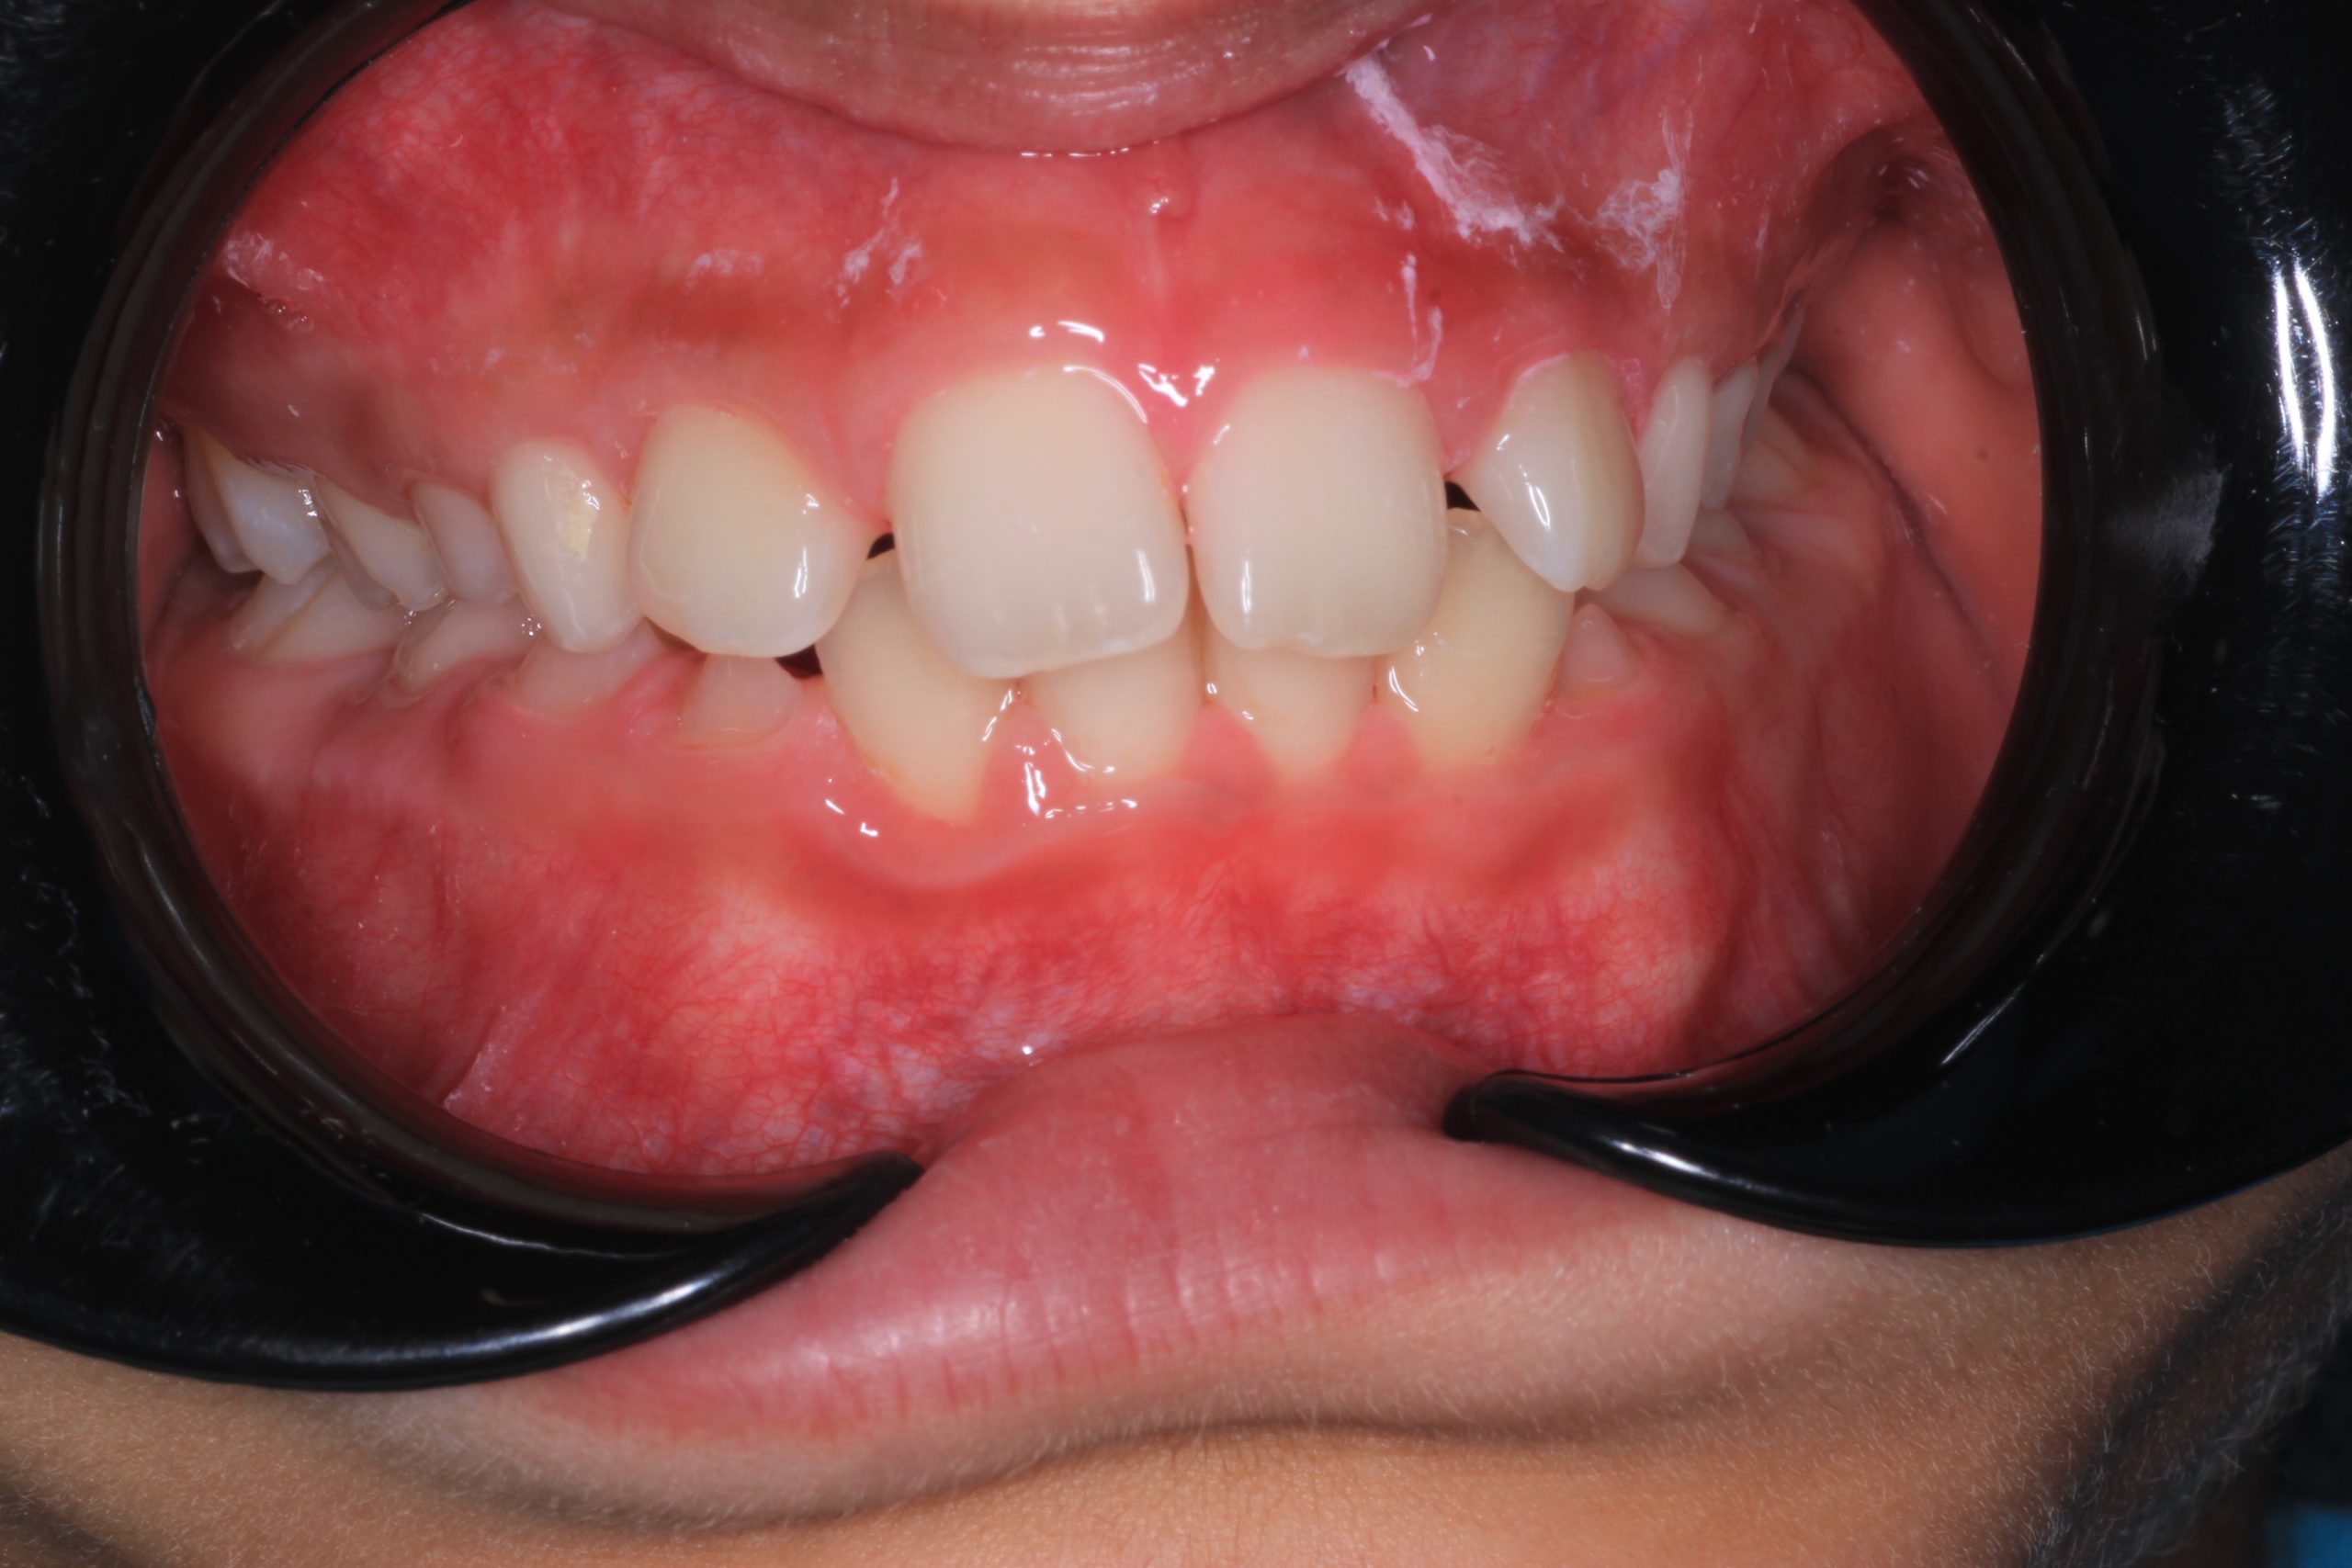

We examine the condition of teeth, gums, and bite. - Plaque Disclosure with Special Indicators

Areas that weren’t cleaned well appear purple. The darker the shade, the older the plaque. This helps both kids and parents understand where brushing needs to improve. - Brushing Training & Home Care Tools Selection